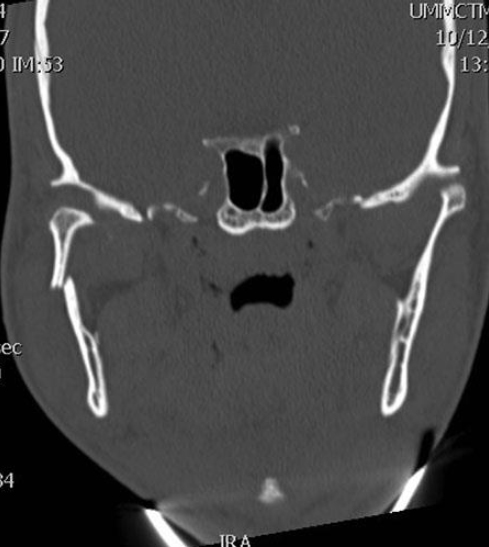

A 16-year-old girl is brought to the emergency department after sustaining fractures to the mandible in a rollover motor vehicle collision. She is intubated during the primary survey because of her critical airway. A CT scan is shown. Which of the following is the most appropriate treatment of this fracture pattern?

The correct response is Option C.

This CT scan shows right–body and left–angle fractures, both with clinically significant displacement. Modern facial fracture management dictates early primary reduction and repair; therefore observation and soft diet without surgery is incorrect, as is avoiding disturbance of the mandible and allowing 6 weeks of bone healing. Since she has reached the age of skeletal maturity permanent titanium hardware is an accepted modality of treatment; therefore it is incorrect to avoid hardware and rely on non-reduced maxillomandibular fixation. In addition, an angle fracture cannot typically be treated with maxillomandibular fixation alone, but requires a Champy plate or more rigid fixation. Open reduction and internal fixation of the right–body fracture, without repairing the left angle is incorrect, as Champy lines do not preclude the need for fixation. Open reduction and internal fixation of both the right body and the left angle fractures is correct, as both fractures need to be reduced, and then fixated, for the best chance of restoring occlusion.